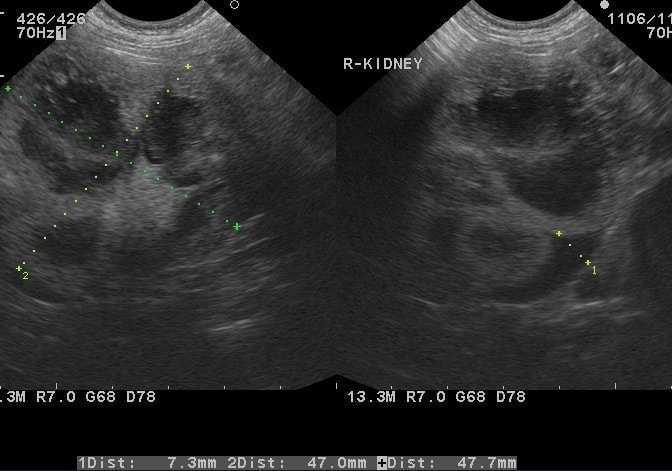

Step 06. エコー(超音波検査)

レントゲンと同様に、『腫瘍を探す』ための検査ですが、エコーは内臓の内部の腫瘍を探します。

腎臓型リンパ腫

左右の腎臓がかなり巨大になっています。細胞診でリンパ腫と確定しました。抗がん治療により腎臓は通常サイズまで縮小しました。